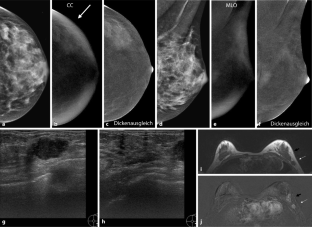

Abb. 1